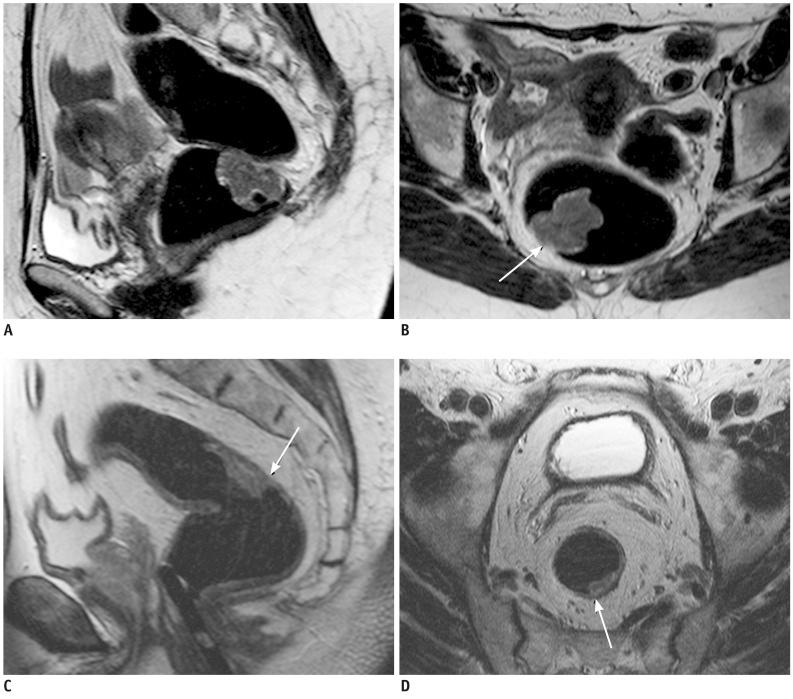

Seventy-three patients with primary rectal cancer underwent high-resolution MRI with a phased-array coil performed using 60-80 mL room air rectal distention, 1-3 weeks before surgery. MRI results were compared to postoperative histopathological findings. The overall MRI T staging accuracy was calculated. CRM involvement prediction and the N staging, the accuracy, sensitivity, specificity, positive predictive value (PPV) and negative predictive value (NPV) were assessed for each T stage. The agreement between MRI and histological results was assessed using weighted-kappa statistics.

The overall MRI accuracy for T staging was 93.6% (k = 0.85). The accuracy, sensitivity, specificity, PPV and NPV for each T stage were as follows: 91.8%, 86.2%, 95.5%, 92.6% and 91.3% for the group ≤ T2; 90.4%, 94.6%, 86.1%, 87.5% and 94% for T3; 98,6%, 85.7%, 100%, 100% and 98.5% for T4, respectively. The predictive CRM accuracy was 94.5% (k = 0.86); the sensitivity, specificity, PPV and NPV were 89.5%, 96.3%, 89.5%, and 96.3% respectively. The N staging accuracy was 68.49% (k = 0.4).

MRI performed with rectal lumen distention has proved to be an effective technique both for rectal cancer staging and involved CRM predicting.